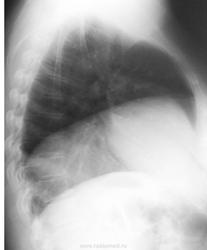

Высокое стояние правого купола диафрагмы.Средостение на месте.На жидкость не похоже.Хотя..на фоне сердца в межодолевой щели видится мне что-то смутно напоминающее оную.Но не факт.

Четко можно говорить о высоком стоянии правого купола диафрагмы - элевации. Причину прежде всего нужно искать в брюшной полости. О релаксации говорить проеждевременно - обязательно должна быть парадоксальная подвижность купола при скопии. Если это есть - занимаемся средстением, диафрагмальным нервом и самим куполом...

На мой взгляд обращает на себя внимание ГЛЖ, бесструктурность корней и высокое расположение правого купола диафрагмы-вызванного скорее всего давлением в брюшной полости, чем снижением его в правом гемитораксе. Приведенные данные полезны, но нужна еще клиника.

На представленных Rg ОГК в двух проекциях, без очаговых и инфильтративных изменений. Легочный рисунок усилен (особенно слева), за счет бронхососудистого компоненка. Корни структурны??? Высокое стояние правого купола диафрагмы - элевация. Сердце увеличено в размерах, за счет левого желудочка. Аорта уплотнена. Требуется исключить патологию органов брюшной полости.

Высокое стояние правого купола диафрагмы. В проекции правого корня дополнительная тень, вероятно имеющаяя отношение к средостению, для того чтобы разобраться, я бы взял пациента на R-скопию( а лучше на КТ, но с этим у нас проблема доступности).

Прямые рентгенологические признаки ТЭЛА:обеднен артериальный сосудистый рисунок правого легкого, расширен корень правого легкого, правая промежуточная артерия не визуализируется, по-видимому, из-за отсутствия кровотока в ней. Косвенные признаки ТЭЛА: высокое стояние правого купола диафрагмы. Если бы присутствовали уплотнения легочной ткани субплеврально( что можно найти при просвечивании), то речь бы шла о симптоме Вестермарка, характерного для ТЭЛА. Учитывая жалобы и клинику, вероятнее всего ТЭЛА.

Могу объяснить как усечён. Снимок лёгочный (то есть не для средостения) и тем не менее хотя бы контурно должен быть виден верхнедолевой бронх – его нет, угадывается короткая, конусовидная культя. Мы также не видим необходимую для нормального корня «головку» с характерным веерообразным разветвлением сосудов в верхней доле, да и «тело» корня укорочено.